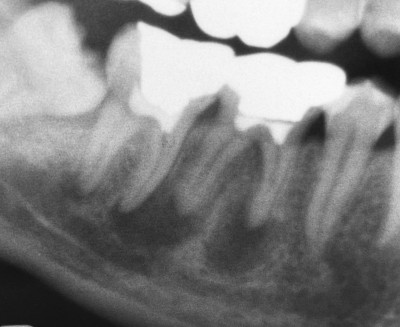

【下顎第二大臼歯】根管治療2年経過